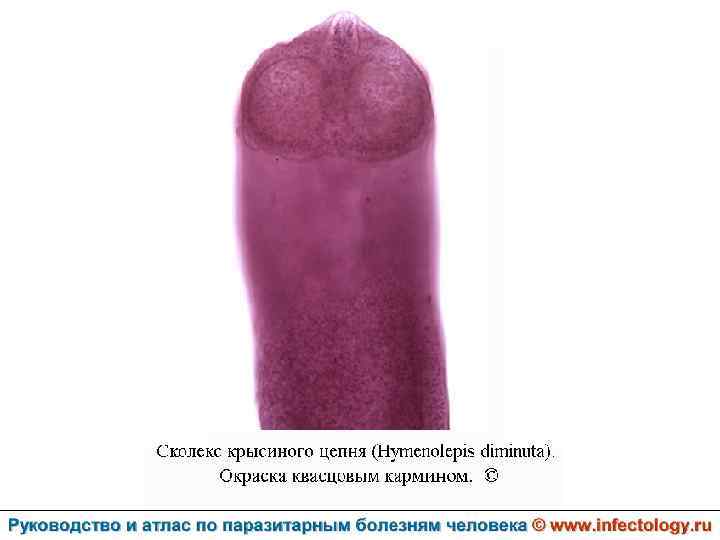

Гименолепидоз крысиный (диминутный) (шифр по МКБ 10 – B 71. 0) – зоонозный гельминтоз, для которого человек является случайным хозяином. Характеризуется нарушением деятельности пищеварительной и нервной систем.